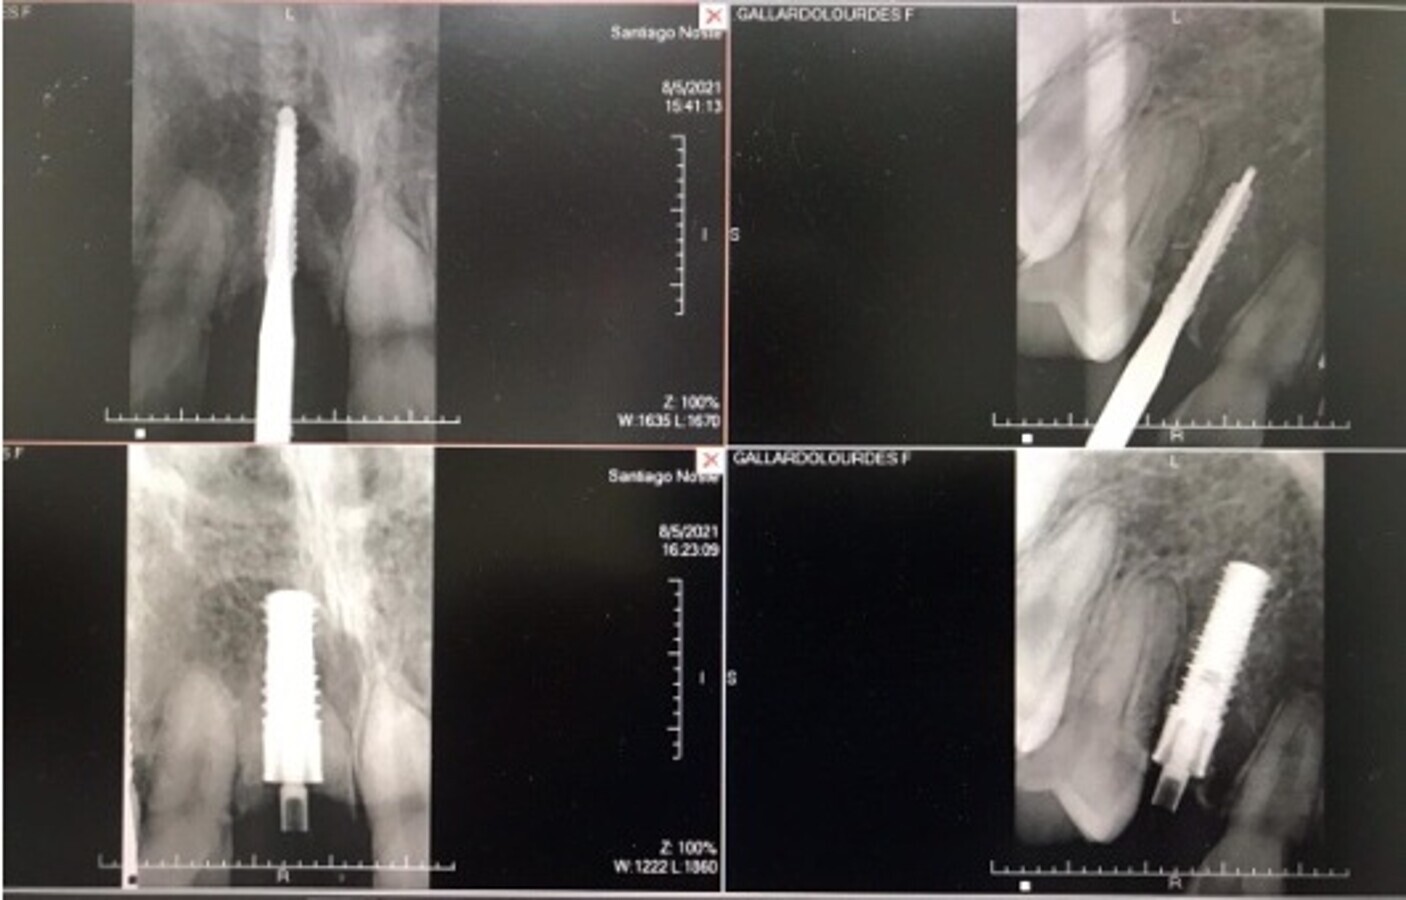

Fig. 2. Tomografía Cone Beam mostrando la reabsorción radicular de 11 y 53.

Fig. 3. Tomografía Cone Beam con las mediciones apropiadas.

Fig. 5. Implante rectos NTI colocados sin realizar incisión ni sutura.